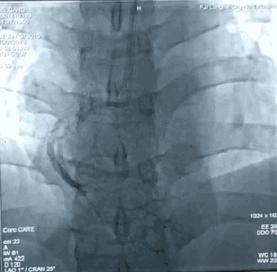

在家里忍了几个小时以后,实在是受不了了,到医院一查,原来是急性下壁心梗,当时已经出现了严重的心律失常,心率只剩36次/分,立即做了急诊介入手术,开通堵塞的血管,恢复还不错,赶在春节前高高兴兴地回家过年去了。